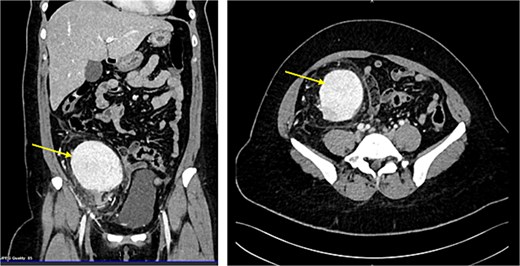

The MRI showed a large right iliac fossa extraperitoneal soft tissue mass, measuring 8.3 × 2.2 × 8.4 cm. The mass shows intermediate T2, low T1, and marked diffusion restriction. Dynamic imaging shows avid early contrast enhancement with retention of contrast in delayed imaging. The original spleen was in its normal place. The uterus showed multiple small intramural and subserosal fibroids with a low T2 signal, and an isointense T1 signal with no diffusion restriction or suspicious enhancement (Fig. 3).

MRI abdomen signifying the mass and its location, extent in both views (Arrow points at the mass).